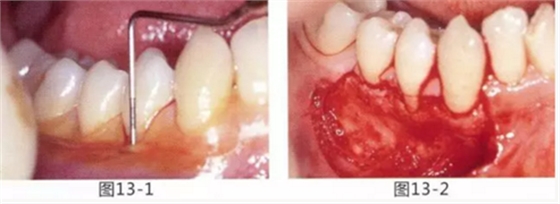

圖13-1 使用碘溶液進(jìn)行染色,頰側(cè)基本看不到角化牙齦,且無口腔前庭的狀態(tài)。

圖13-2 為了擴(kuò)張口腔前庭,獲取附著齦而進(jìn)行了游離齦移植術(shù)。受皮床一定不能發(fā)生移動(dòng),盡可能使厚度均等。

圖13-3 手術(shù)剛結(jié)束的狀態(tài)。通過骨膜縫合的褥式縫合將移植片固定,使其無法移動(dòng)。

圖13-4 手術(shù)完成2年后的狀態(tài)。口腔前庭得到擴(kuò)張,即使正在進(jìn)行正畸治療,也沒有妨礙到清潔。